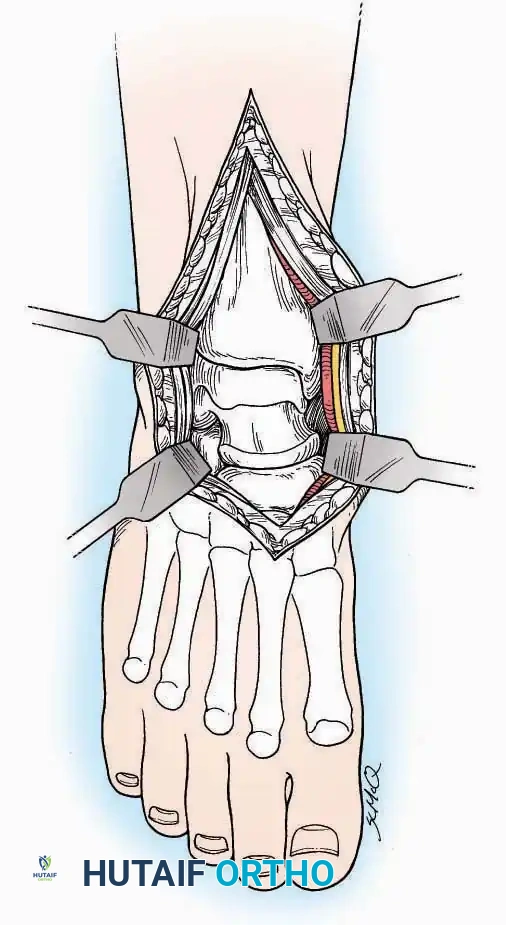

SURGICAL APPROACHES TO THE TARSUS AND ANKLE

Anterolateral Approach

The anterolateral approach is widely considered the "universal incision" for the foot and ankle. It provides unparalleled access to the ankle joint, the talus, and the majority of the tarsal articulations, while safely avoiding the major anterior neurovascular bundle. The only tarsal joints inaccessible via this route are the naviculocuneiform joints (specifically the medial and intermediate).

Indications: Total talectomy, triple arthrodesis, ankle arthrodesis, and open reduction of complex talar neck fractures.

Surgical Technique:

* Incision: Begin over the anterolateral aspect of the leg, medial to the fibula and 5 cm proximal to the ankle joint line. Carry it distally over the joint, crossing the anterolateral aspect of the talar body and the calcaneocuboid joint, terminating at the base of the fourth metatarsal.

* Superficial Dissection: Incise the superficial fascia and the superior and inferior extensor retinacula down to the periosteum of the tibia and the ankle joint capsule.

* Vascular Ligation: This trajectory usually requires the identification and ligation of the anterolateral malleolar and lateral tarsal arteries.

* Nerve Protection: Retract the skin edges carefully. Identify and protect the intermediate dorsal cutaneous branches of the superficial peroneal nerve (SPN), which frequently cross the distal aspect of this incision.

* Muscle Management: Identify the origin of the extensor digitorum brevis (EDB) muscle on the lateral calcaneus. Divide it in the direction of its fibers, or detach its origin entirely and reflect it distally to expose the subtalar and calcaneocuboid joints.

* Deep Exposure: Retract the extensor digitorum longus (EDL) tendons, the dorsalis pedis artery, and the deep peroneal nerve (DPN) medially. Incise the anterior ankle capsule to expose the tibiotalar joint.

* Tarsal Exposure: Expose the talonavicular joint by dissecting deep to the extensor tendons and incising its capsule transversely. Continue laterally through the capsule of the calcaneocuboid joint. By excising the fat pad within the sinus tarsi (lateral and inferior to the talar neck), the posterior facet of the subtalar joint is brought into direct view.

Anterior Approach

Indications: Total ankle arthroplasty (TAA), anterior ankle arthrodesis, and excision of anterior tibial/talar osteophytes (anterior impingement).

Surgical Technique:

* Incision: Make a 10 to 15 cm longitudinal incision over the anterior aspect of the ankle, centered exactly midway between the medial and lateral malleoli.

* Superficial Dissection: Incise the superficial fascia. Identify and protect the superficial peroneal nerve branches laterally and the saphenous nerve medially.

* Internervous Plane: The deep dissection exploits the plane between the Extensor Hallucis Longus (EHL) tendon (innervated by the deep peroneal nerve) and the Extensor Digitorum Longus (EDL) tendons (also innervated by the deep peroneal nerve).

* Neurovascular Bundle: Incise the extensor retinaculum. Carefully identify the anterior tibial artery and the deep peroneal nerve, which typically lie between the EHL and EDL, or directly deep to the EHL. Retract the neurovascular bundle laterally with the EDL, or medially with the EHL, depending on the specific anatomical variant encountered (lateral retraction is most common).

* Capsulotomy: Incise the anterior joint capsule longitudinally. Elevate the capsule subperiosteally from the anterior tibia and the talar neck to expose the entire tibiotalar articulation.